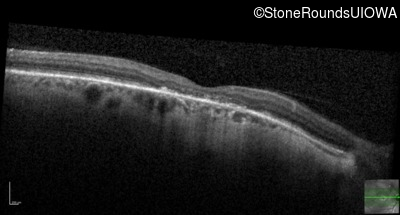

This 52 year old man had normal vision until his mid 30's when he began to have trouble distinguishing colors. the issuing 10 years he had a gradual loss of visual acuity accompanied by increasing photophobia.

| Age at visit: 55 years |

| Age at visit: 58 years |

| Age at visit: 61 years |

| Age at visit: 64 years |